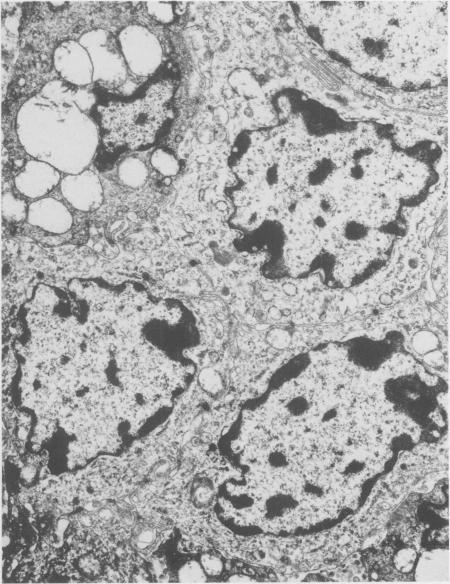

Eight bovine, two ovine and one porcine primary hepatocellular neoplasms were found during a five year survey of tumors from meat packing plants. The tumors varied in size and usually were yellow-grey. Some were encapsulated and divided into lobules by fibrous septa. The tumor cells closely resembled normal hepatocytes and were arranged in a trabecular pattern or in sheets with caverns or were a mixture of the two. Eosinophilic intranuclear inclusions were present in one bovine and one ovine case.